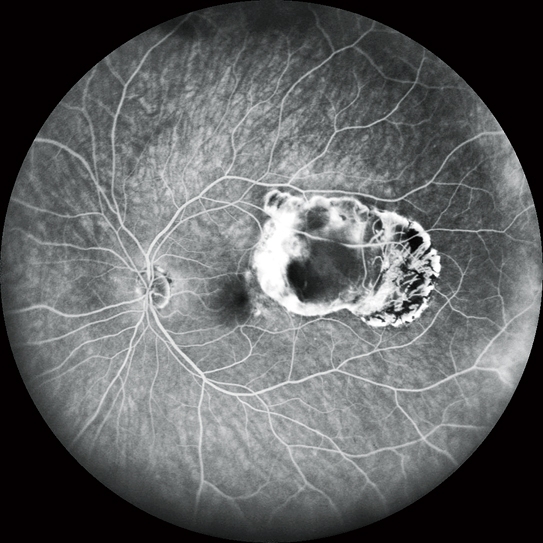

FA和ICG *

高清動態血管造影

可錄制分辨率高達1,024 x 1,024像素,最長時長為120秒的視頻。在同一次測量中也可分段錄制多個短視頻。

FA和ICG同步血管造影

Mirante操作簡便,可同步拍攝FA和ICG影像。實時IR監測方便操作者在熒光產生前調整拍攝位置,降低錯過血管造影早期階段的風險。

自動增益控制(AGC)可同步調整各個FA和ICG圖像的對比度,使動態血流成像成為一個非常簡便的過程。

* 適用于SLO/OCT型。SLO型可選。